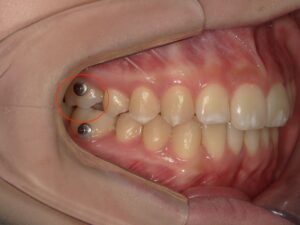

凸凹を治したいという希望の患者様です。

こちらの患者様も、スペース不足によって前歯が凸凹になってしまっています。

顎の側方骨幅に余裕があり、

「歯列の側方拡大」とIPR(歯の側面を0.5mm以内で削る)という方法のみで

非抜歯矯正で治療をすることとしました。